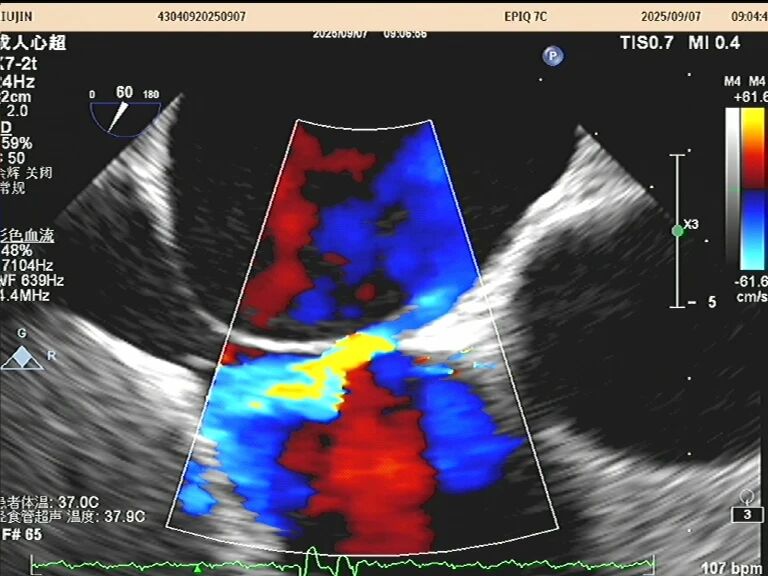

于是,一根如面条般柔软、顶端带着微型摄像头的探头,会从您的口腔缓缓进入食道。这个位置堪称完美,探头能紧贴着心脏,利用超声波为其拍摄一场无死角、超高清的“内部直播”。以前藏在背后的细微结构比如心耳里是否藏有血栓、人工瓣膜是否严丝合缝、心脏瓣膜上的小赘生物,此刻都一览无余。

这场大约15-20分钟的“心脏之旅”,价值巨大。它是诊断许多复杂心脏问题的“金标准”,如同为医生点亮了一盏明亮的探照灯,直击病灶。无论是指导心脏手术、排查脑卒中元凶,还是评估重症患者的心脏功能,它都提供了最关键的依据。